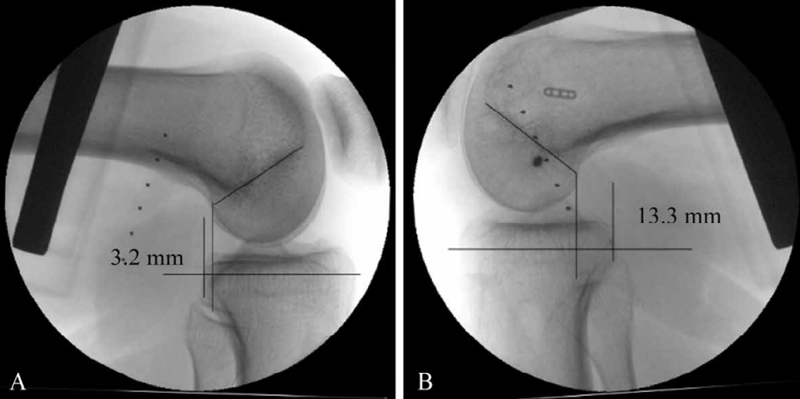

后方应力位或跪位X线检查是诊断PCL损伤的可靠方法(图6),对比健侧,后移增加0~7mm为PCL部分损伤(图7),8~11mm为单纯PCL全部断裂(图8),12mm以上可能为PCL和PLC等其他结构合并损伤(图9)。

图7 PCL部分损伤X线影像

应力位X线片(B)示胫骨后移超过健侧(A)5mm

图8 PCL完全断裂X线影像

应力位X线片示患侧(B)胫骨后移超过健侧(A)10.1mm

图9 PCL完全断裂合并PLC损伤X线影像

应力位X线片示患侧(B)胫骨后移超过健侧(A)13.5mm